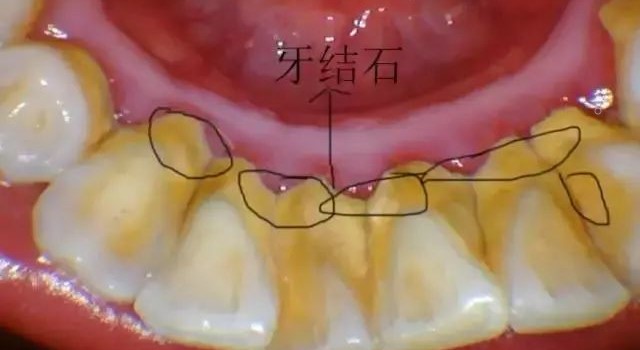

洗牙是一种通俗的说法,它的医学名称叫做龈上洁治术,是用器械从牙面上去除菌斑、牙石,并抛光牙面的一种治疗方法。下面小编主要探讨目前最主流的超声波洁牙。

首先,我们要明白超声洁牙后的最初几天,感觉牙齿对冷热酸甜敏感是一种正常情况,这叫做牙本质敏感。原因很简单,原来牙齿有藏污纳垢的牙齿包裹,牙龈经常发炎、牙龈出血,牙骨质也可能被破坏了;洗掉牙石后,牙齿恢复原貌,但由于牙龈退缩导致牙根位置的牙本质暴露出来,一碰到冷热酸甜就会让人酸软不适。

4、定期洁牙:常年积累的牙结石又多又硬,以致洁牙时需要加大洁牙机的强度才能去除,这样会加重牙齿酸痛感。半年、一年或者两年定期洁牙,在牙结石小的时候形成的量不多,质较松,很容易去除,这样定期洁牙就不易造成洁牙时的酸痛感。

其实这是一种感觉上的错觉。洗牙后之所以让人容易有牙缝变大的感觉是因为在洗牙的过程中,把堆积在牙龈表面、牙缝间的牙结石通过超声波震动方式震碎、清除,而使得舌头在碰触牙齿时,不再受到牙结石干扰,可直接碰触牙缝所致。其实,这些牙缝是本身早已存在的,与洗牙并无关。